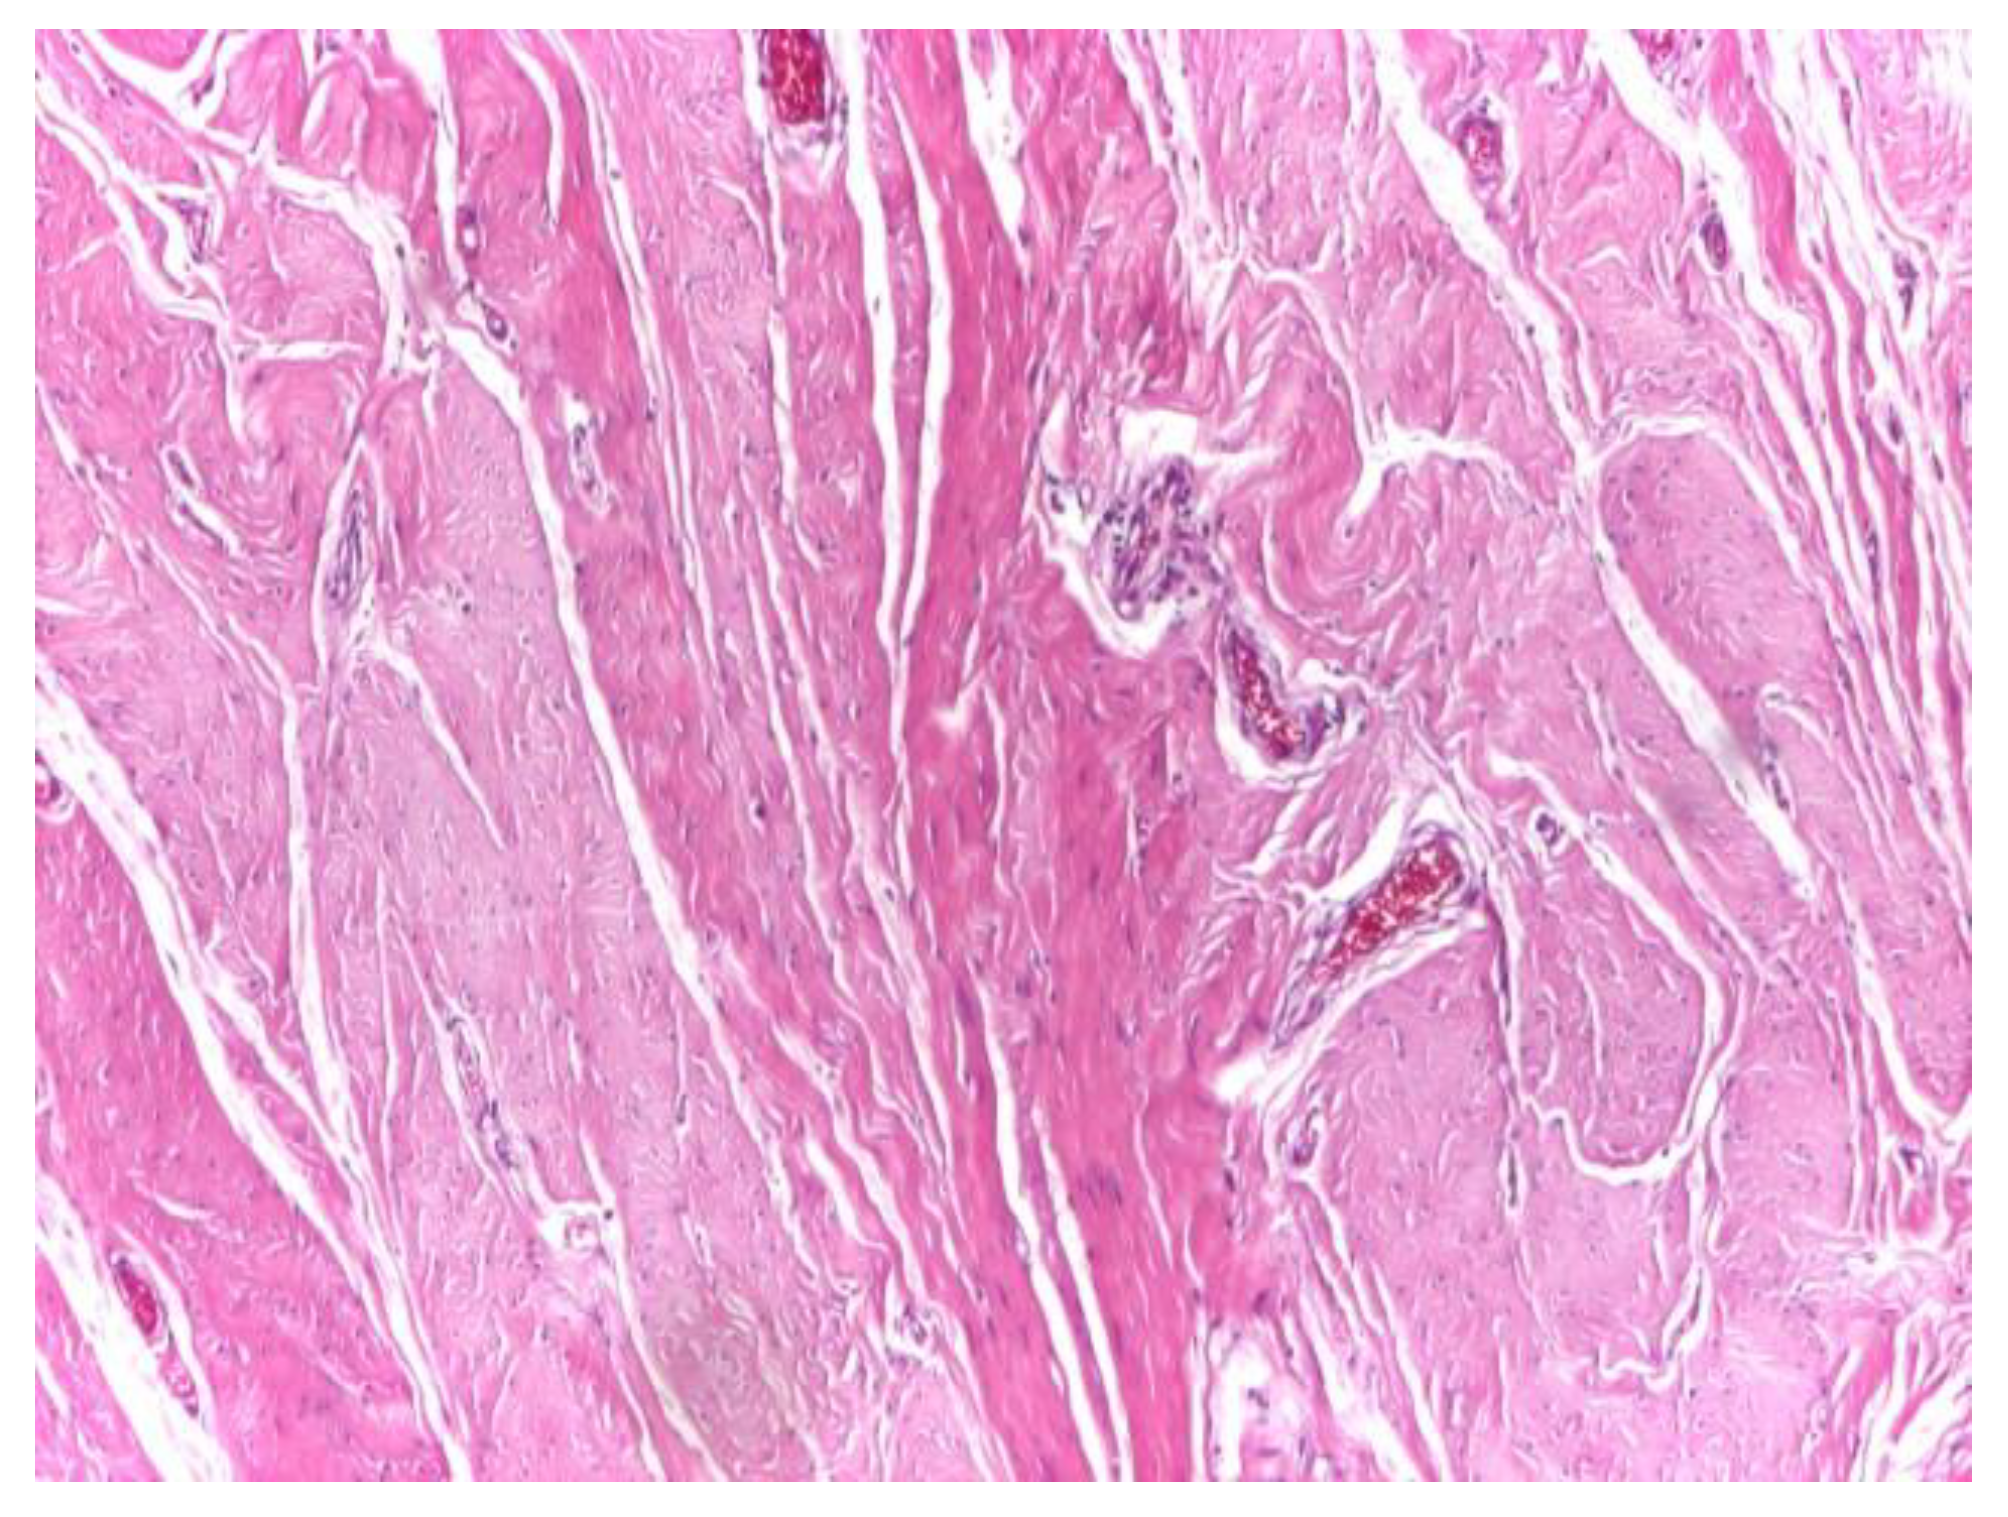

Optical microscopy of human aponeurotic tissue revealed a well-preserved connective architecture characterized by dense, predominantly parallel collagen fiber bundles forming an organized structural framework. At low magnification (×4), the aponeurotic fragments displayed a compact and continuous collagenous matrix with a clear preferential fiber orientation, consistent with the load-bearing function of the abdominal wall aponeurosis (Figure 1).

Figure 1. Representative low-magnification optical micrograph of human aponeurotic tissue highlighting parallel and orderly arranged collagen fiber bundles. Hematoxylin and eosin staining (H&E); original magnification ×4.